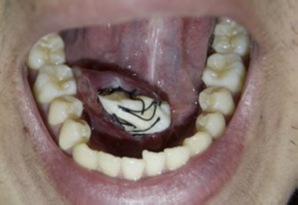

Se decide su tratamiento quirúrgico conservador siguiendo el protocolo de la técnica de marsupialización modificada. Bajo anestesia local (articaína 4%) con bloqueo directo del nervio lingual ipsilateral, se realizó la transfixión con hilo de sutura no absorbible seda 4,0 (Silk®) en la superficie de la mucosa del piso de la boca con los bordes de la lesión. Después de delimitar el campo se realizó una incisión aguda de la mucosa y cápsula a lo largo de su eje mayor (pared superior de la ránula). Con la incisión hecha y la retirada de la pieza para estudio histopatológico, se vació el contenido mucoso, permitiendo la resección de la parte superficial del quiste. Se introdujo con un elemento de contención impregnado con antiséptico intralesional (gasa impregnada en Furacín®) para que no colapse la cavidad quística, la cual se sutura en la periferia para impedir su desalojo con los movimientos (fig. 3). Se indicó irrigar la cavidad con clorhexidina al 0,12% 10 ml 2 veces al día por 10 días. Como tratamiento farmacológico se le indicó amoxicilina comprimidos 500 mg cada 8 h por 7 días, e ibuprofeno 600 mg cada 8 h por 3 días. Para su control y seguimiento se citó a los 3, 7 y 10 días (fig. 4). Al décimo día se eliminó el elemento de contención (fig. 5). Se realizó un seguimiento clínico por 12 meses, sin observarse signos de recidiva de la lesión (fig. 6).

La marsupialización modificada descrita por Baurmash9 consiste en empaquetar un taponamiento de gasa dentro de la lesión luego de eliminar la pared quística superior y suturar dicha membrana a la mucosa del piso de la boca, generando una solución de continuidad. El elemento de contención debe ser mantenido entre 7 y 10 días, siendo un requisito indispensable para el éxito de la técnica, ya que produce una respuesta inflamatoria induciendo la formación de una fibrosis y sello permanente con remisión de la lesión.

En este caso la gasa fue impregnada con un antibacteriano tópico de amplio espectro perteneciente a la familia de los nitrofuranos (Furacín®) por 10 días, ya que sin esta gasa los bordes tienden a colapsar debido a la presencia de un espacio muerto sumado a los movimientos de la lengua, dando como resultado una alta probabilidad de recurrencia10. El mecanismo de acción de la gasa estaría en su capacidad de inducir, a través de una reacción inflamatoria al cuerpo extraño, una atrofia acinar11.

Otro factor a considerar es la utilización de sutura como guía quirúrgica, ya que permite una delimitación anatómica adecuada como garantía de la integridad del marco de la lesión12.